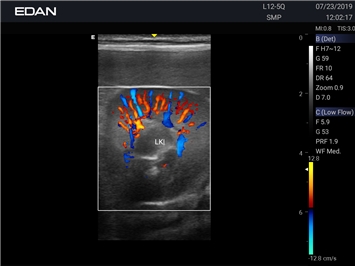

Энергетический допплер:

Да

Цветовой допплер:

Трехмерная реконструкция ЦДК: